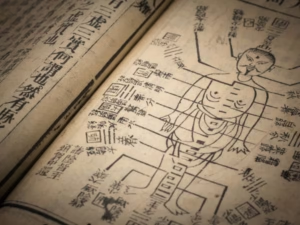

La acupuntura es una herramienta de la medicina china clásica que utiliza la inserción de agujas finas en puntos de acupuntura para regular funciones fisiológicas, activar la circulación y estimular mecanismos internos de autorregulación del cuerpo.